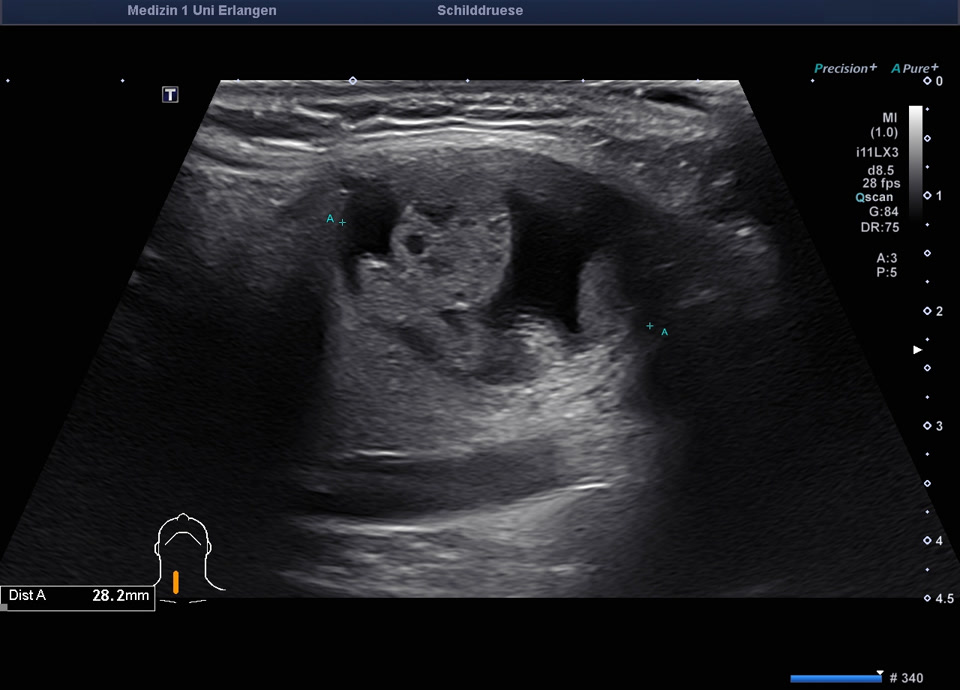

78-jähriger Patient mit Zufallsbefund einer hypodensen Schilddrüsenläsion im Rahmen eines Kardio-CTs vor geplanter Aortenklappenoperation. In der sonographischen Abklärung zeigte sich eine normal große Schilddrüse mit einem 2 cm echoarmen Knoten (EU-TIRADS 4), farbdopplersonographisch ohne relevante intranoduläre Durchblutung. Die Elastometrie zeigte eine erhöhte Gewebesteifigkeit. Der TSH-Wert lag im Normbereich, klinisch bestanden keine Hinweise auf eine Schilddrüsenerkrankung. Es erfolgte eine ultraschallgesteuerte Stanzbiopsie sowie eine Feinnadelpunktion mit zytologischer Aufarbeitung (Zytospin). Histologisch ergab sich ein follikulärer Knoten. Kommentar des Pathologen: anhand der Biopsie kann eine follikuläre Neoplasie nicht sicher von einem autonomen Adenom unterschieden werden. Zur funktionellen Abklärung (zum Nachweis eines autonomes Adenom) sollte eine Schilddrüsenszintigrafie erfolgen. Aufgrund der vorausgegangenen Kontrastmittelgabe (Kardio-CT) ist eine Schilddrüsenszintigrafie erst nach ≥8 Wochen möglich. Vorrangig erfolgt zunächst die Behandlung der hochgradigen Aortenstenose. Nach Durchführung der Szintigrafie ohne Nachweis eines Adenoms sollte aufgrund des Risikos einer follikulären Neoplasie eine operative Abklärung (diagnostische Hemithyreodektomie) erwogen werden. Alternativ sind sonographische Verlaufskontrollen nach 6 und 12 Monaten möglich.